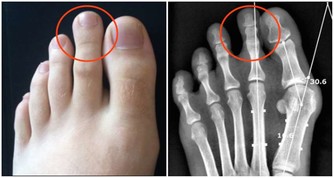

小孩擠眉弄眼,有黑眼圈家長要引起重視

小朋友因為好動,日常會有很多小動作,很多家長會不以為然,但如果發現寶寶長期以往臉部有奇怪的表情,那就要引起注意了,寶寶很可能是患上過敏性鼻炎了。

以下症狀,如果出現其中一個症狀,家長都應注意觀察或到專業醫院諮詢,做好兒童過敏性鼻炎的預防工作:

1.一到春季或秋季,頻繁的打噴嚏流鼻涕

2.黑眼圈大而重

3.夜裡睡覺時張口呼吸打呼嚕

4.習慣性揉鼻子、揉眼睛、擠眉弄眼

5.容易出現皮膚瘙癢